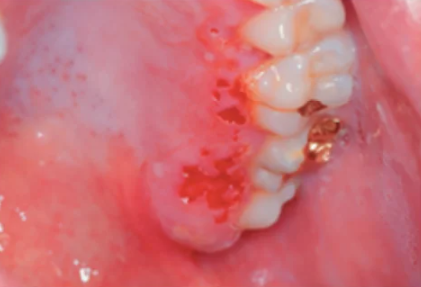

- 歯周膿瘍(ししゅうのうよう)

- 原因: 歯周病が進行し、歯周ポケット(歯と歯ぐきの間の溝)に細菌が溜まって炎症を起こし、膿がたまることでできます。

- 特徴: 歯ぐきが赤く腫れ上がり、触るとブヨブヨしていて、痛みや発熱を伴うこともあります。ひどくなると膿が出てくることもあります。